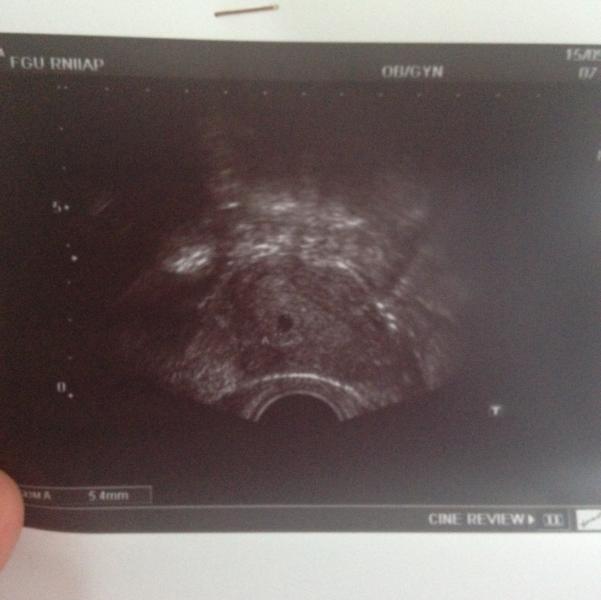

Вот и прошло мое первое УЗИ! Неописуемые ощущения и переживания! Ходила одна, коленки потряхивало перед кабинетом, абсолютно нормальные переживания, всё ли в порядке, всё ли там на месте и как надо! 🙈 Доктор, которая делала УЗИ такая молоденькая, но очень милая и вежливая, мне сразу понравилась. К слову, наблюдаюсь в 4-Й поликлинике. Ну вот, сначала смотрела датчиком через животик, когда она произнесла, что в полости матки обнаруживается "один плод, живой...", мне уже дальше просто половину даже...

Год назад я увидела свою горошинку и рыдала от счастья, не только потому что мы планировали и ждали ребеночка, но и потому, что первая неделя, несмотря на полосатый тест не хотела никак показывать малыша на узи. Прошел всего год, нл сколько всего в нем было - первый тест, первое узи, первый раз услышала сердечко моей крохи, анализы, визиты к врачу, первый скрининг и эти пляшущие ножки на узи 😍 тонус, второй скрининг и новость о том, что это доченька, тонус, первое 3д фото малышки, слезы радости ...